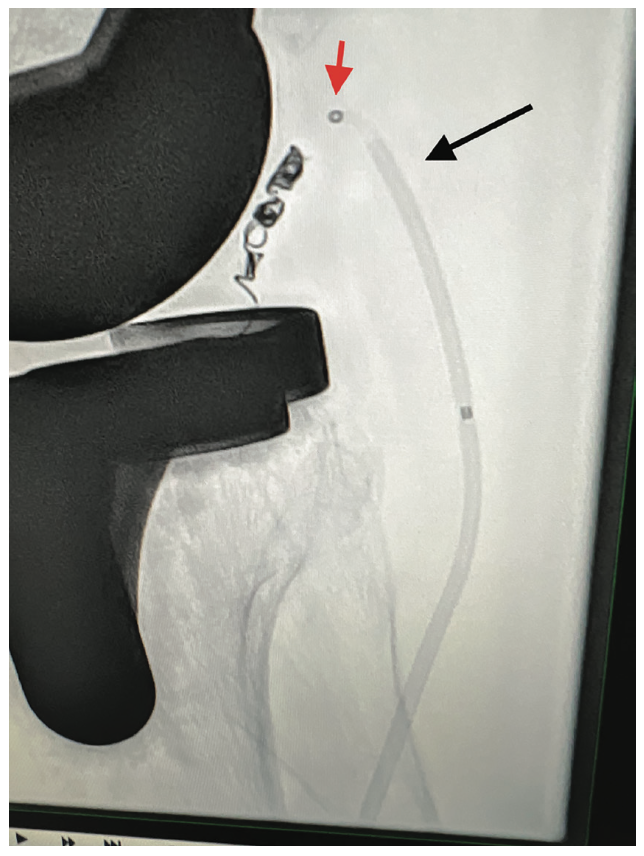

The left common femoral artery was accessed, the right external iliac artery was selectively engaged, and an angiogram was performed for delineation of the popliteal artery and its branches (Figure 2). Transpedal access was then obtained to the right anterior tibial artery for a better approach to the acute upward angle takeoff of the inferior genicular artery. A multipurpose catheter was then advanced to the level of the P2 segment of the popliteal artery. Using a combination of an .014 Advantage Glidewire (Terumo Interventional Systems) and Cantata Microcatheter (Cook Medical), the lateral inferior genicular artery was selected and the catheter was advanced to the intraluminal position. Two coils, a 2 mm x 7 mm Nester coil (Cook Medical) and then a 2 mm x 2 mm Nester coil, were deployed in standard fashion (Figure 3). Subsequent angiography showed successful coiling of the lateral inferior genicular branch. The microcatheter and multipurpose catheter were removed (Figure 4). Hemostasis was obtained using manual pressure for the right transpedal access and Angio-Seal (Terumo Interventional Systems) for the left femoral artery.